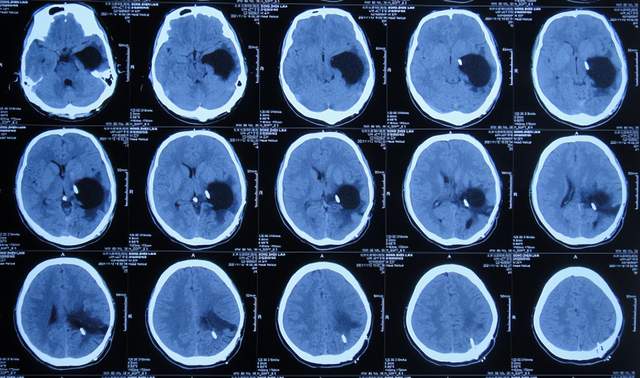

2021年2月5日(脑膜瘤切除术后颅内感染3周)住入李小勇脑脊液科,入院时:精神差,食欲差,体温高(图-13);查头颅CT示脑瘤术后状态(图-14);(外院)2021年2月3日头颅核磁示有脑脓肿(图-12)。

图-13:2021年2月5日入院时

图-14:2021年2月5日头颅CT

入院后3天即2021年2月8日,左颞角脑室腹壁外引流术(图-15)。

图-15:2021年2月8日头颅CT

左颞角脑室腹壁外引流术后8天即2021年2月16日,查头颅CT示颞角缩小(图-16)。

图-16:2021年2月16日头颅CT

左颞角脑室腹壁外引流术后21天即2021年3月1日,查头颅CT示颞角仍有扩张(图-17)。

图-17:2021年3月1日头颅CT

左颞角脑室腹壁外引流术后23天即2021年3月3日,头颅CT增强和核磁增强示有脑脓肿(图-18、图-19)。

图-18:2021年3月3日头颅CT增强

图-19:2021年3月3日头颅核磁增强

2021年3月8日(左颞角脑室腹壁外引流术后28天),进行了脑脓肿切除术(图-20)。

图-20:2021年3月8日头颅CT

2021年3月9日(左颞角脑室腹壁外引流术后29天,脑脓肿切除术后次日),查头颅CT示脑脓肿切除术后(图-21)。

图-21:2021年3月9日头颅CT

2021年3月11日(左颞角脑室腹壁外引流术后31天,脑脓肿切除术后4天),患者身体状态良好,体温变正常(图-22)。

图-22:2021年3月11日

2021年3月12日(左颞角脑室腹壁外引流术后32天,脑脓肿切除术后5天),查头颅CT示仍有少量水肿(图-23)。

图-23:2021年3月12日头颅CT

2021年3月26日(左颞角脑室腹壁外引流术后46天,脑脓肿切除术后19天),夹闭引流管1周左右,颞角没有扩张,因此进行了脑室腹壁外引流管拔除术。

但拔除引流管后11天即2021年4月6日,患者出现头痛,查头颅CT示颞角扩张(图-24)。

图-24:2021年4月6日头颅CT

因此于2021年4月8日,进行了脑室腹腔分流术;术后身体一切正常(图-25)。

图-25:2021年4月9日

于2021年4月18日(治疗近3个月)出院,出院时:身体一切正常。